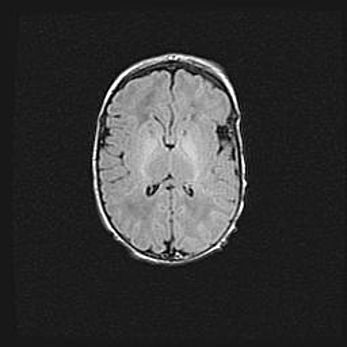

Сообщающаяся гидроцефалия. Кистозная энцефаломаляция головного мозга.

Возраст: 3 месяца 4 дня

Вес: 3100 г

Пол: женский

Окружность головы: 34 см

Срок гестации: 31 неделя

Кистозная энцефаломаляция головного мозга - одна из форм поражения головного мозга в детском возрасте. Характеризуется возникновением множественных и распространённых кист в коре, белом веществе и подкорковых образованиях головного мозга у плодов, новорождённых и детей раннего возраста. Развитие кистозной энцефаломаляции связано с внутриутробной асфиксией и гипотонией, родовой травмой, тромбозом синусов, пороками развития сосудов, инфекциями, сепсисом и другими причинами. Наиболее значимые инфекционные агенты: вирусы простого герпеса, цитомегалии, краснухи, токсоплазмы, энтеробактерии, золотистый стафилококк и другие.